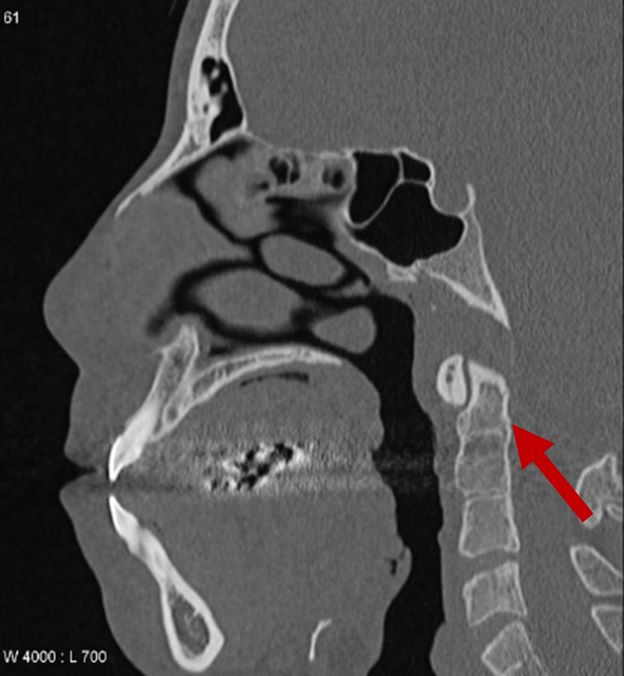

Fused vertebrae

2D CT scan showing fused 2nd and 3rd vertebrae

Radiographical features source 9